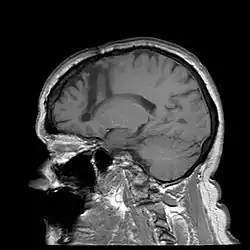

One of the most notable treatments for the brain occurring in the 20th century was the lobotomy, which was invented in 1935 by Portuguese Neurologist Egas Moniz.[28] The lobotomy was a surgical procedure performed on the brain that targeted the frontal lobe, which is the part of the human brain that controls emotional response. The reason the lobotomy targeted this particular lobe was to reduce stress and other negative emotions to cure disabilities.[29]